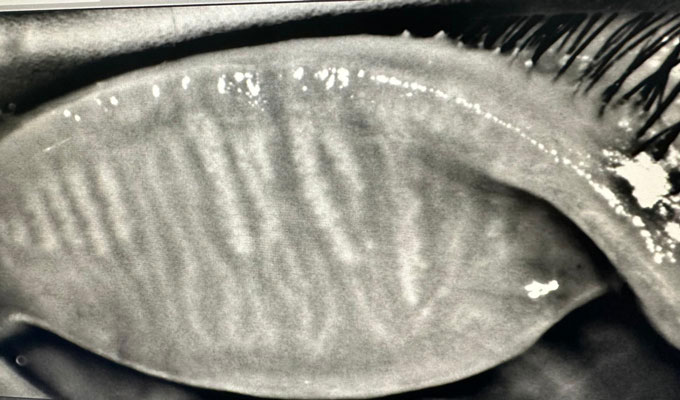

Non-invasive blepharoplasty

Blepharitis

Entropion

Acting on the cause rather than the symptoms

Towards targeted, sustainable treatment.

RF and IPL mainly rely on heat emission and gland expression to treat Meibomian Gland Dysfunction (MGD), stimulate collagen, and heat the Meibomian glands, Jett goes further. It also affects several other aspects of the ocular surface, influencing various mechanisms that contribute to dry eye and inflammatory conditions.

Jett technology directly stimulates the goblet cells responsible for mucin production, reducing excessive evaporation and contributing to better lubrication of the eye. It also supports the proper function of the orbicularis muscle to improve blink efficiency, which is essential for the even distribution of tears. By acting on the laxity of the lower eyelids and the Riolan muscle, it optimizes eyelid closure and tear distribution, thus reducing dryness.

Furthermore, with its new protocols, Jett stimulates the accessory lacrimal glands of Krause and Wolfring, which are responsible for producing the aqueous component of the tear film, promoting optimal aqueous secretion. It also strengthens local conjunctival immunity, an essential system for protecting the ocular surface. Finally, it acts on cell regeneration, improves meibum quality, and creates an astringent effect that enhances the function of the Meibomian glands. These combined mechanisms allow for a comprehensive, non-invasive management of dry eye and inflammation control.